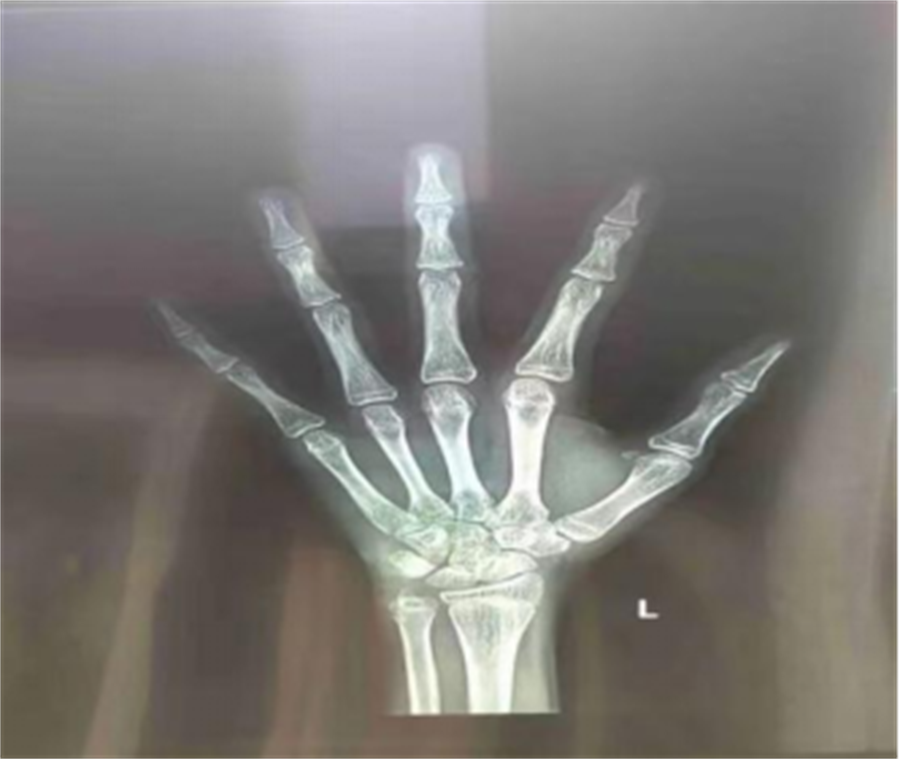

骨龄:骨龄全称骨骼的年龄,它是以小儿骨骼实际发育程度同标准发育程度进行比较,所求得的一个发育年龄。骨龄在很大程度上代表了儿童真正发育水平。

人类骨骼发育的变化基本相似,每一根骨头的发育过程都具有连续性和阶段性。不同阶段的骨头具有不同的形态特点,骨龄评估能较准确地反映个体的生长发育水平和成熟程度。